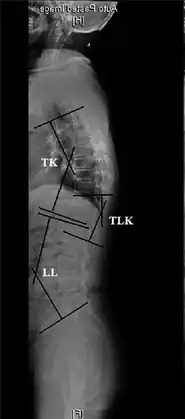

TK: Thoracic kyphosis- Measurements of spinopelvic parameters -

Sagittal balance measurement.[7]